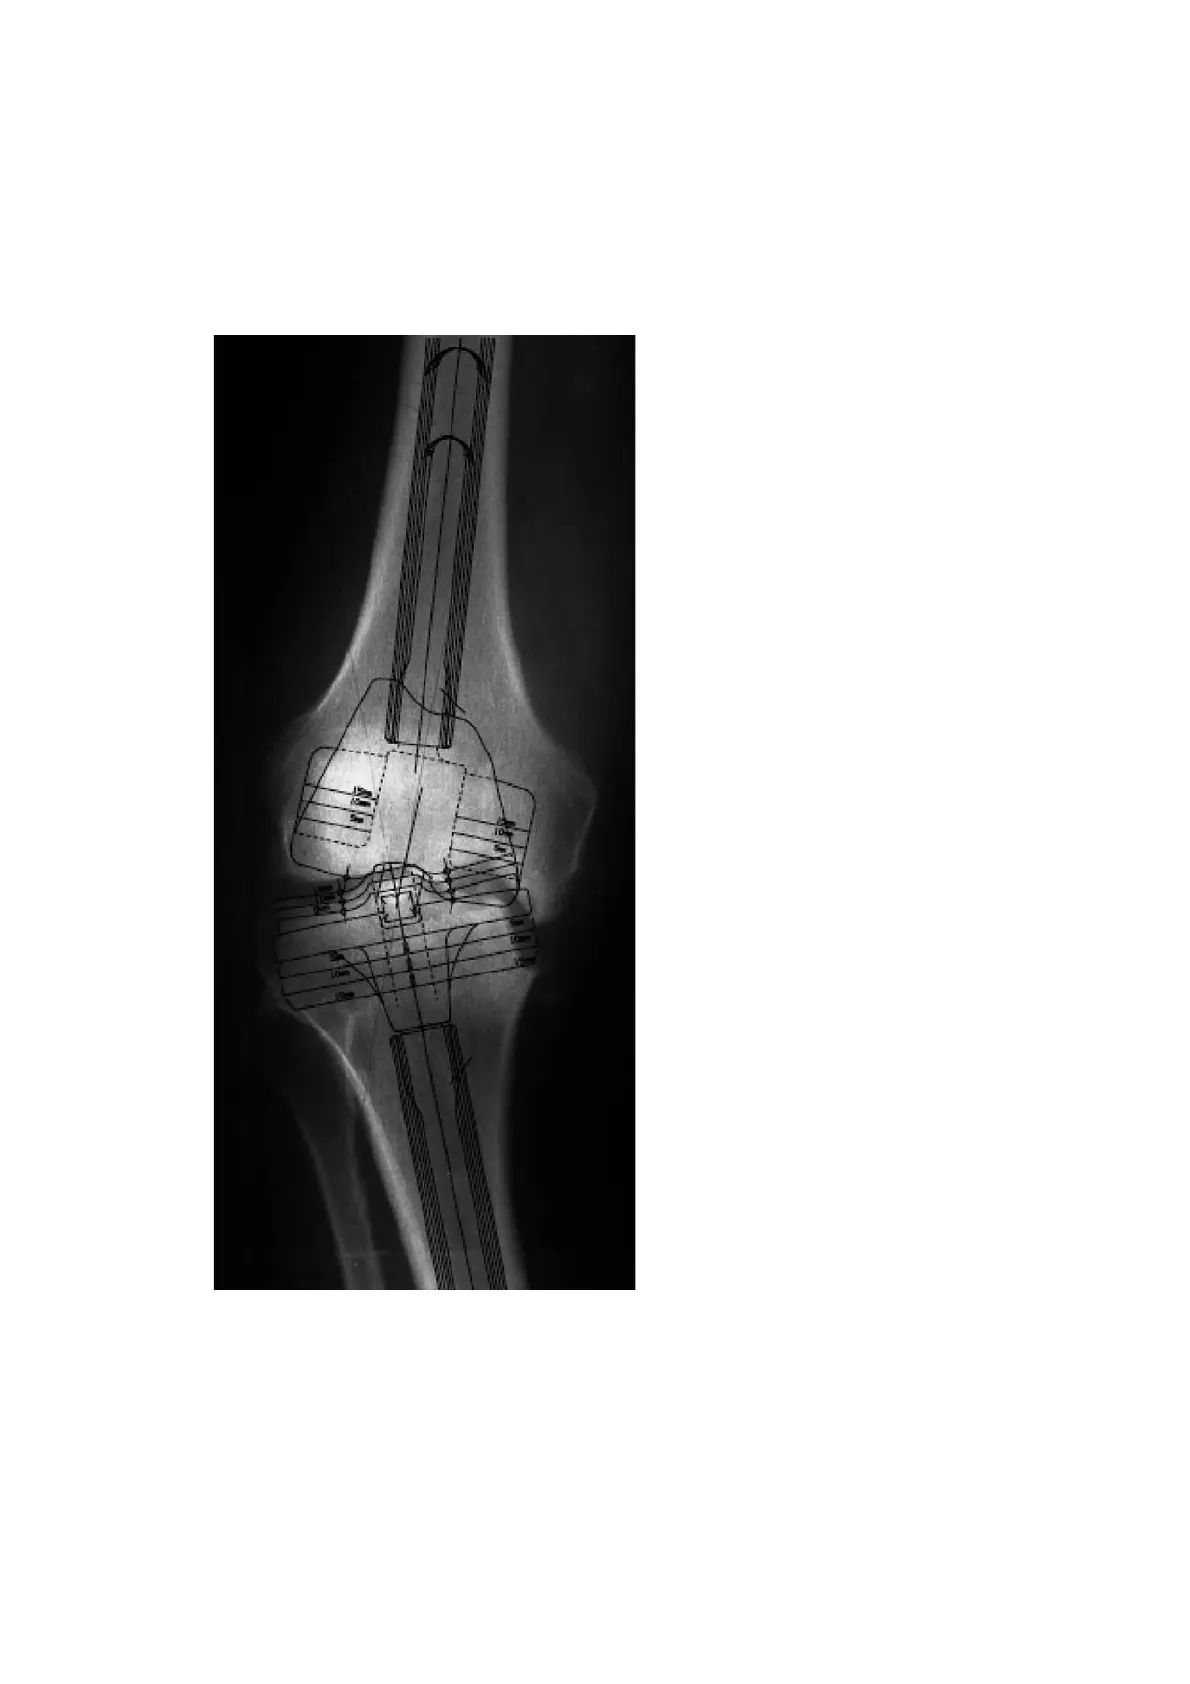

A full-leg X-ray with the patient in the standing position is recommended for preoperative-

planning purposes. If this is not possible, an X-ray of the thigh, including the femoral head,

should be taken. The X-ray images of the knee joint at three levels should be available for

planning the surgery. A tangential patellar exposure, a frontal and a sagittal to the leg axis

exposure must be taken.

For preoperative planning there are X-ray tem-

plates available: with scale of 1.15:1 Lit. No. 1135

and with scale of 1:1 Lit. No. 1584 (see page

74). The lateral view of the condyles is deci-

sive. If these are no longer completely intact,

it is possible to switch to the condylar width.

In cases of doubt, the smaller implant should

be selected to prevent the prosthesis com-

ponents from protruding. In normal cases,

the size determination and the correct posi-

tioning of the prosthesis are controlled intra-

operatively with relevant instruments, and

planning may also be possible on the unre-

stored opposite side leg.